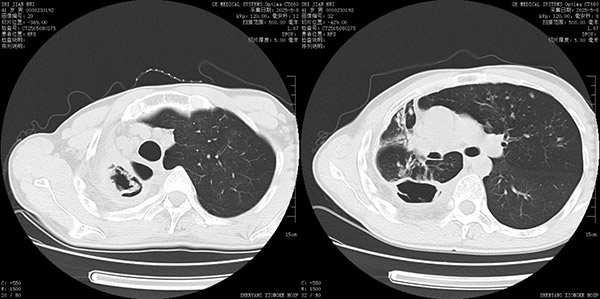

真菌性肺空洞因病灶位置深、药物渗透难,导致传统全身用药存在疗效差、肝肾损伤风险高等痛点。医院呼吸科团队创新开展"纤支镜下超选择注药导管置入技术",通过直径仅2mm的超细注药导管,在CT引导下精准手绘定位病灶,将注药导管超选择性插入病变内部,实现抗真菌药物的局部高浓度灌注。以实现加大局部病灶组织药物血药浓度,降低全身副反应,缩短空洞闭合时间的治疗目的。

接受治疗的张先生(化名)为复发性真菌感染患者,既往结核病史,遗留肺内空洞,现因合并肺内曲霉菌感染,因反复咳嗽、咳痰,发热、咯血多次住院治疗。患者自述经济及心理均承受较大压力。

2025年5月12日入住呼吸与危重症五病区,经多学科讨论、多篇学术文献论证以及患者知情同意下,拟定气管镜下,肺内空洞留置导管并经导管注入抗真菌药物治疗方案。

留置导管后即刻,即经留置导管向空洞内注入两性霉素B抗真菌治疗。

患者留置导管后无不适,每日经留置导管向空洞内注入两性霉素B。抗真菌药物直达病灶,有的放矢,提高肺组织血药浓度。经过一周的治疗,患者咳嗽、咳痰明显减轻,发热症状消失,病情好转出院。